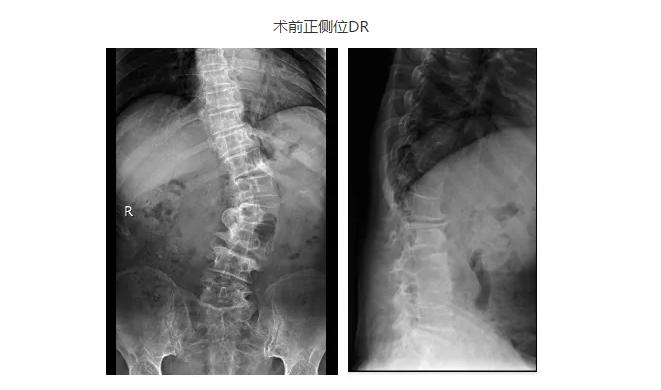

手术历时5个小时,当杨永军副院长走下手术台时,手术衣的后背已经完全被汗水浸透。术后拍片可见王大姨侧弯畸形得到明显纠正,而经过2周顺利拆线后,王大姨佩戴胸腰支具已经可以顺利下地。出院时王大姨激动的握住杨院长的手说:“感谢杨院长给了我第二次生命,让我可以做一个正常人。”